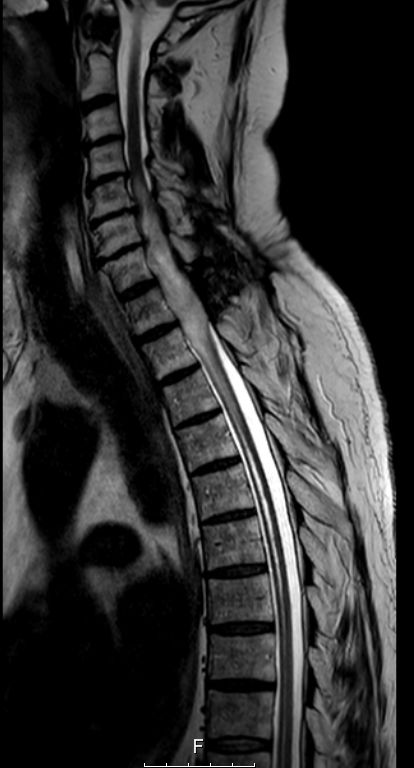

Myelon 63-jähriger Mann mit Querschnittssymptomatik. Auch nach Dekompression keine Motorik oder Sensorik der unteren Körperhälfte.

MRT T1W-Bild